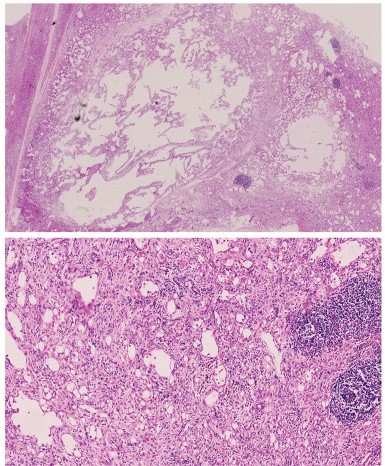

Characteristics observed in the tissue samples of adrenal adenomatoid tumors. Fig 2. Histological features associated with adrenal adenomatoid tumor.2,3